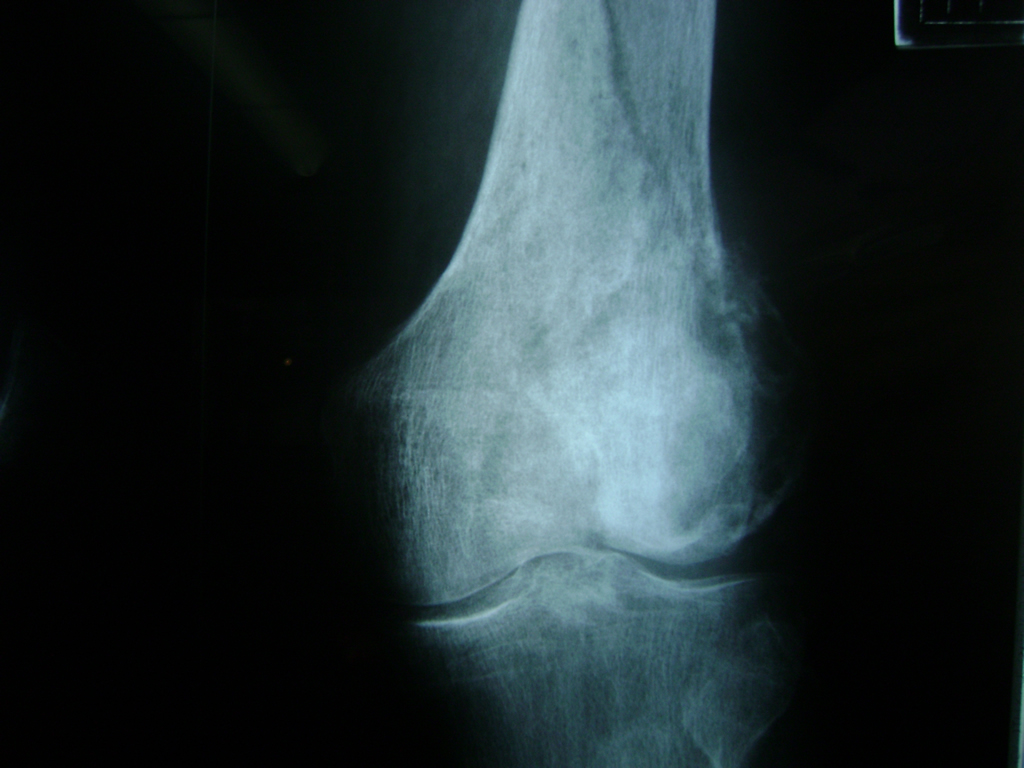

Cirugías de Rodillas

La artroscopia de rodilla es un cirugía en el cual la estructura interna de la articulación es examinada ya sea para realizar un diagnostico o para realizar un tratamiento, este procedimiento se realiza utilizando un instrumento parecido a un pequeño tubo llamado artroscopio.